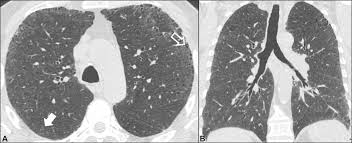

Morphologic classifications of lung conditions diffuse interstitial lung diseases in particular have been undertaken both at the microscopic pathologic patterns and gross radiographic or thin-section computed tomographic CT patterns level. Reticular nodular high and low attenuation table. The lung interstitium is the space where the air sacs called alveoli come in contact with connective tissue and blood vessels to exchange oxygen and carbon dioxide.

In ILDs scarring damages tissues in or around the lungs air sacs and airways. On HRCT there are four patterns.